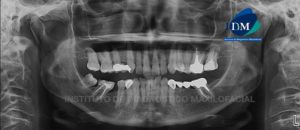

Paciente de sexo masculino con 38 años de edad, acude al Instituto de Diagnostico Maxilofacial para evaluación imagenologica de la pieza 27. A la evaluación